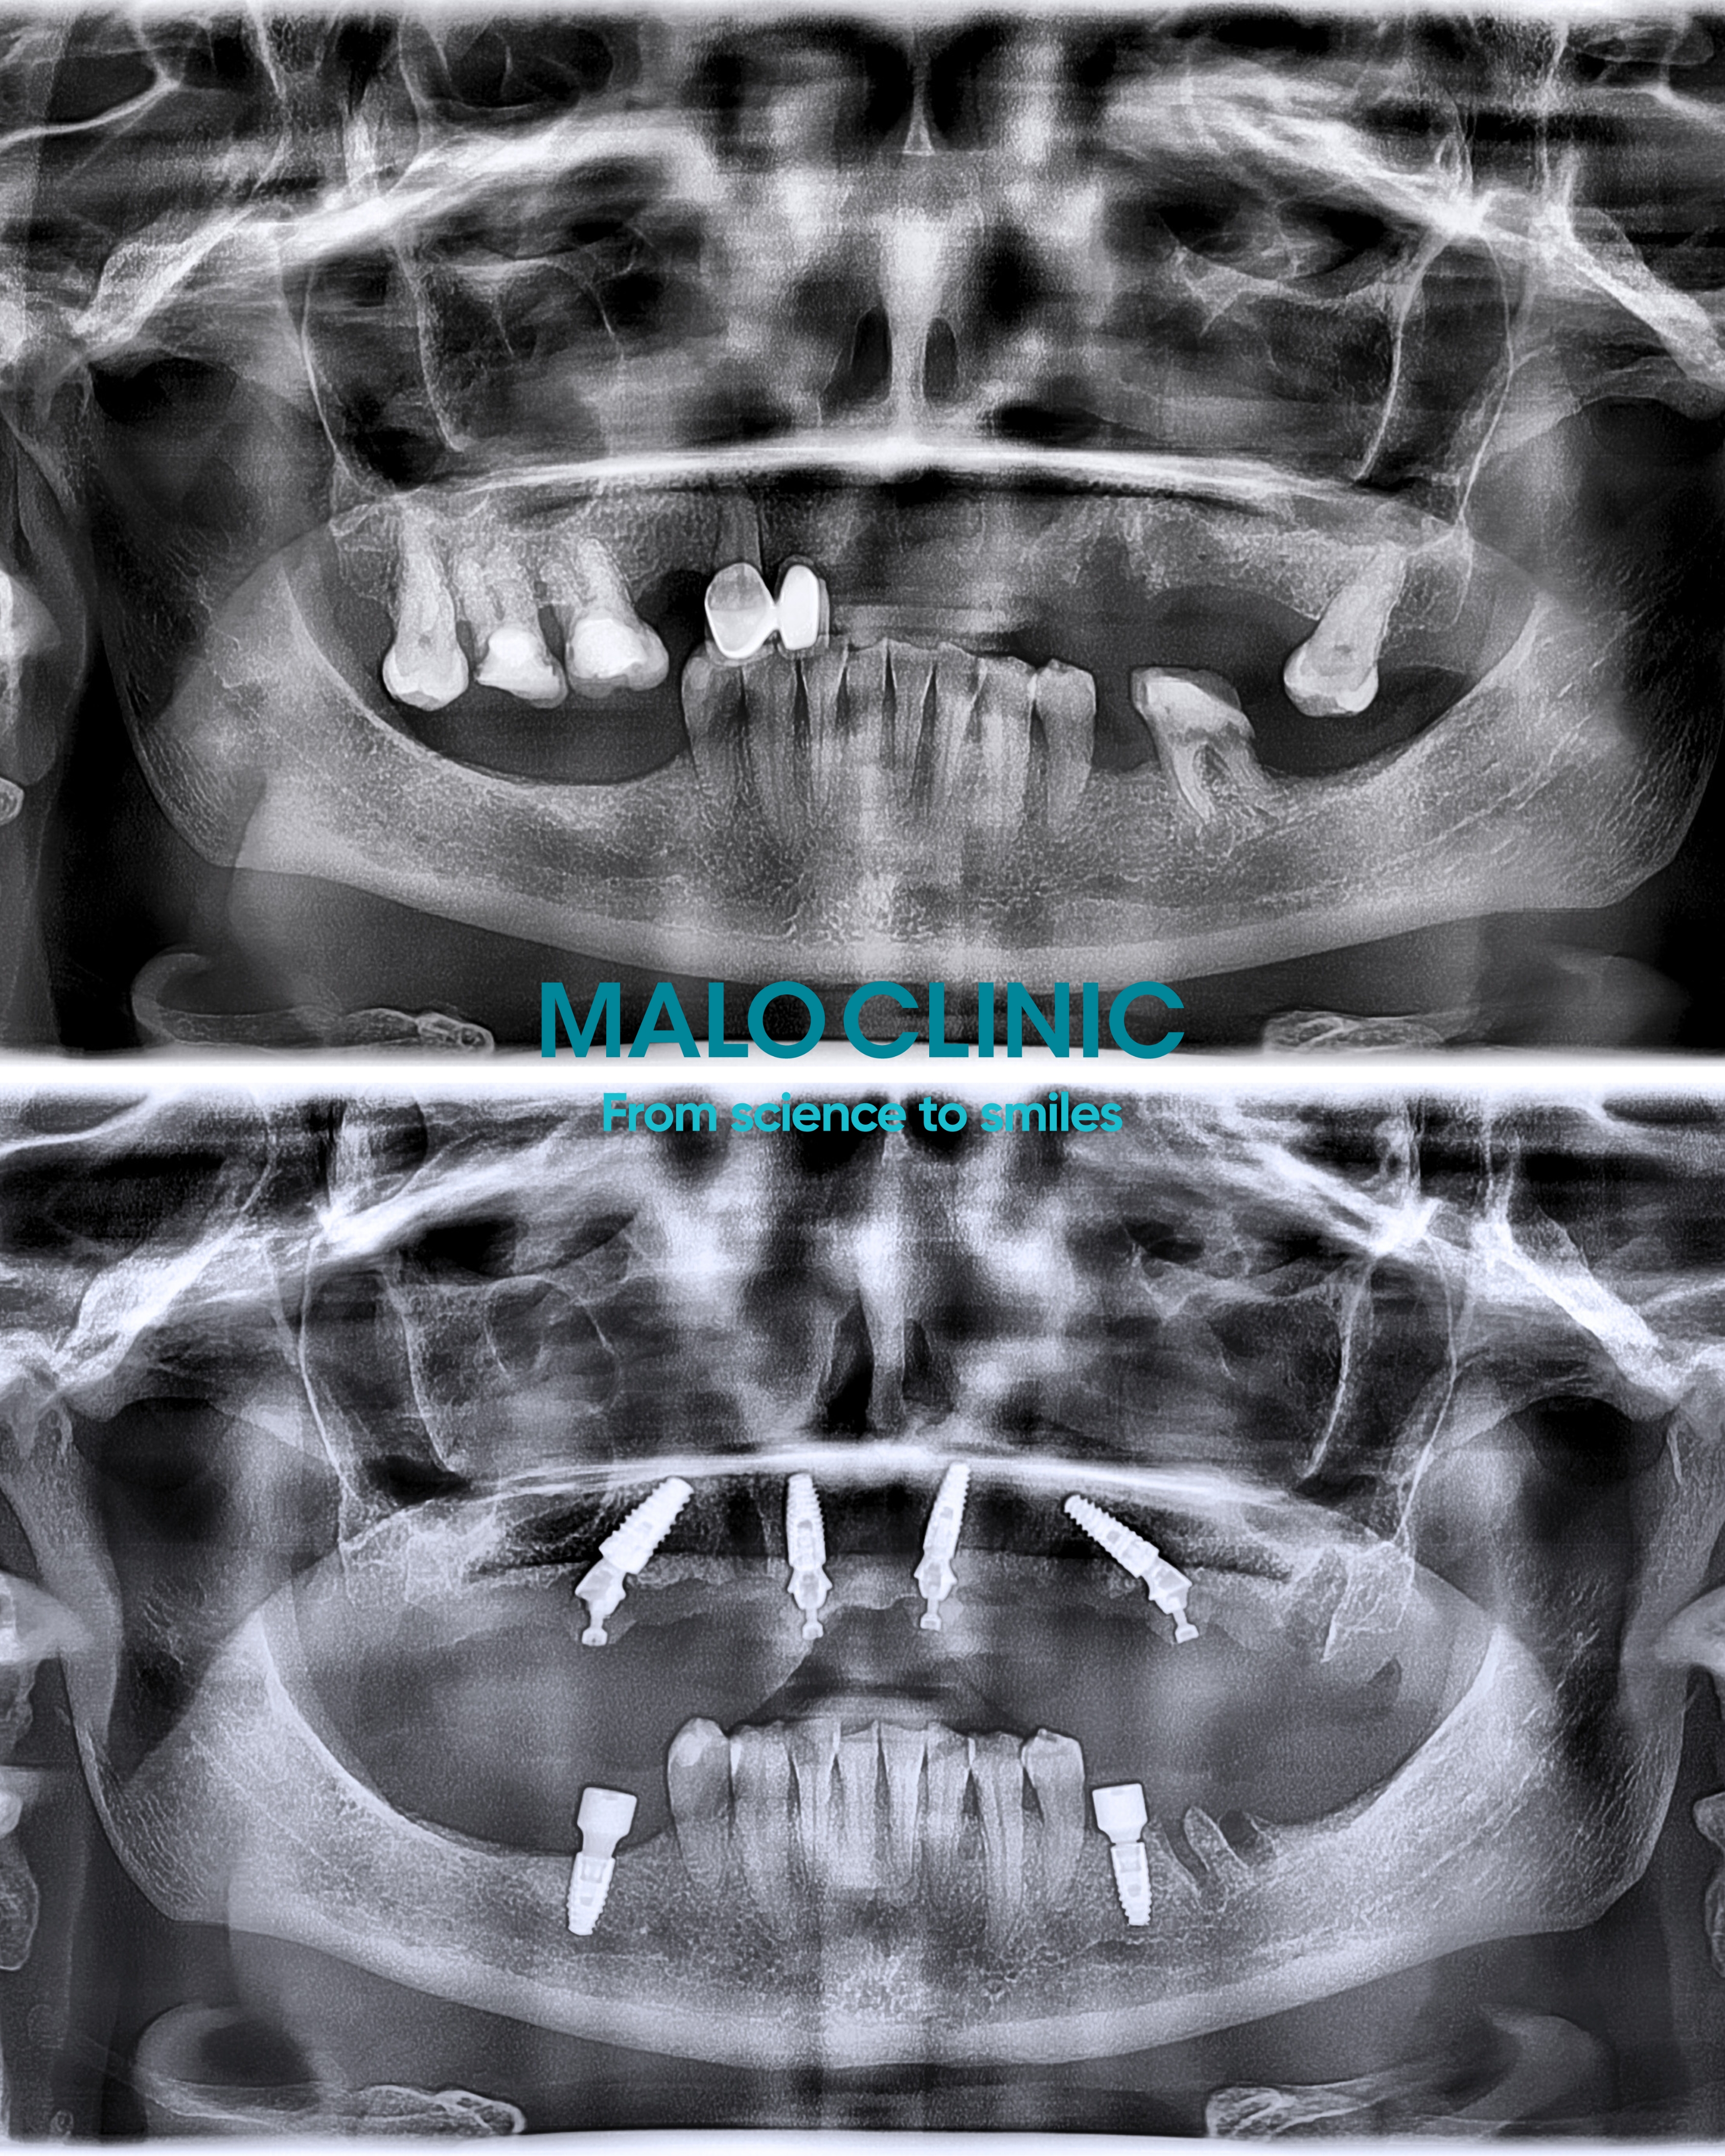

– „Ma Pani jeszcze kilka zębów, jednak nie możemy ich wykorzystać” - wyjaśniał dr Armando Lopes, dyrektor medyczny Malo Clinic Polska, pokazując zdjęcie RTG. - „Są one znacznie obniżone po prawej stronie, a dodatkowo brakuje w szczęce wielu zębów. Konieczne będzie usunięcie pozostałych korzeni i zębów, a następnie wszczepienie czterech implantów, na których odbudujemy stałe uzupełnienie protetyczne”.

Lekarz zaprezentował model mostu opartego na czterech implantach i omówił przebieg leczenia zgodnie z procedurą Malo Clinic Protocol.